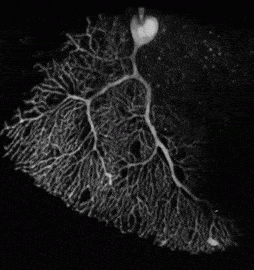

Para mi, fue algo muy importante la presentación de mi taller, con el mismo nombre del artículo que en breve se publicará. Es importante, pues es dar una continuidad al trabajo que por los años 60 comenzó Jaime Rojas Bermudez. Mis coetáneos, pertenecientes a otras ramas del saber, la biología, la neuropsicología y la neurofisiología, hemos rescatado a los «les enfants terribles» (mujeres y hombres) de la Neurociencia, ellas y ellos se merecen resplandecer ya que un nuevo paradigma sobre el animal humano» y sobre su estar en el mundo esta emergiendo y autoras y autores que se encontraban en la sombre están viendo la luz…

«Es el siglo del cerebro y el Sicodrama no puede estar al margen de ello, sobre todo teniendo en cuenta la “teoría del núcleo del yo (Rojas Bermúdez) que es en definitiva una teoría del neurodesarrollo y que centra su metodología en el funcionamiento encefálico. Se relacionará los últimos avances y descubrimientos en neurociencias con la teoría y metodología sicodramática. El encuentro y el desencuentro entre personas tiene sus bases neurofisiológicas y esto lo veremos a través de la metodología sicodramática».